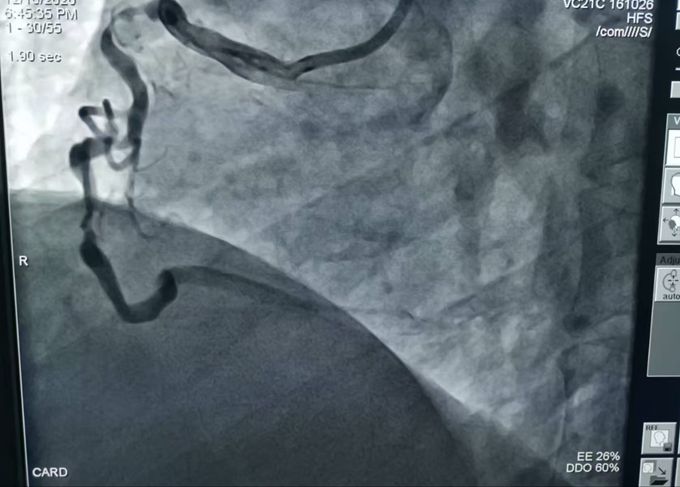

秦楚网-十堰头条讯 文、图/记者 秦洪涛 特约记者 马婷婷 报道:“当时,我们医生都有点吃惊,心脏三支主血管均有严重弥漫性钙化病变且出现不同种度的堵塞,其中两支最重狭窄为次全闭塞,离急性心肌梗死仅一步之遥,情况十分危急。”近…